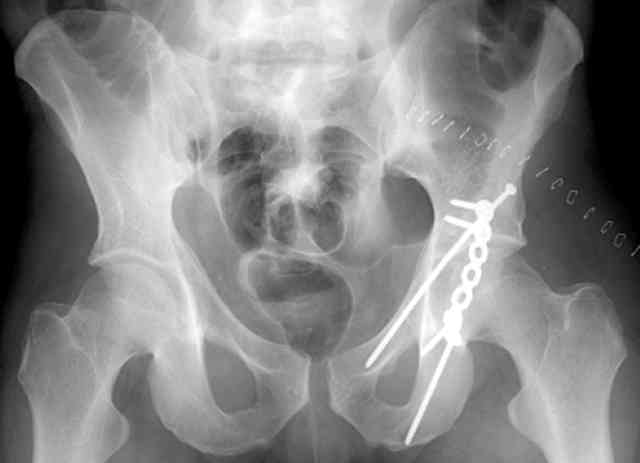

I'll include a few images of a similar injury in a similarly large male patient. This patient "showed up" in our ER c/o hip pain 2 months after being treated in the lateral position, without a quality reduction, without an anterior column transverse supporting implant, with an unbalanced plate applied too medially, with insufficient caudal segment fixation...it took over 8 hours and a 3+ l blood loss to debride the callus from front then

back, excise the HO, release his sciatic nerve, reduce the head-transverse-wall, and fix it...and now it's a staging procedure.

The 2nd example is of a motorcyclist with a transverse fracture-dislocation...he had a closed attempted reduction and placed in traction but the manipulative reduction was not concentric (not unusual for this injury pattern)...so the traction was adjusted to be just enough to disengage the head from the fracture (12#) until he could be cleared for surgery one day after injury...he was treated "urgently" then with a prone KL, clean the fracture, reduce and clamp it, screw it, support with a balanced plate, close, and enjoy...2-3hours, 400cc EBL, blah, blah, blah..